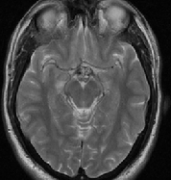

近几十年来,由于在临床实践中广泛使用磁共振成像(MRI)的诊断进展, 脑海绵状血管畸形 (CCM)的发生率有所增加(患病率0.4-0.9%),主要是诊断发年...

脑海绵状血管瘤(CH)报道发现于中枢神经系统的任何部位。由于计算机断层扫描和磁共振成像的使用越来越多,近年来诊断出了更多的先天性心脏病。然...

为什么脑干海绵状血管瘤如此难以治疗?近几十年来,随着磁共振成像(MRI)在临床实践中的广泛应用,脑海绵状血管瘤(CCM)的发病率有所上升(0.4-0.9%)。脑干海...

脑干海绵状血管瘤症状有哪些?脑干海绵状血管瘤怎么治疗? 脑海绵状血管瘤(cerebral cavernous hemangioma,CCM)是异常大的低流量血管集合。McCormick(1966)认...